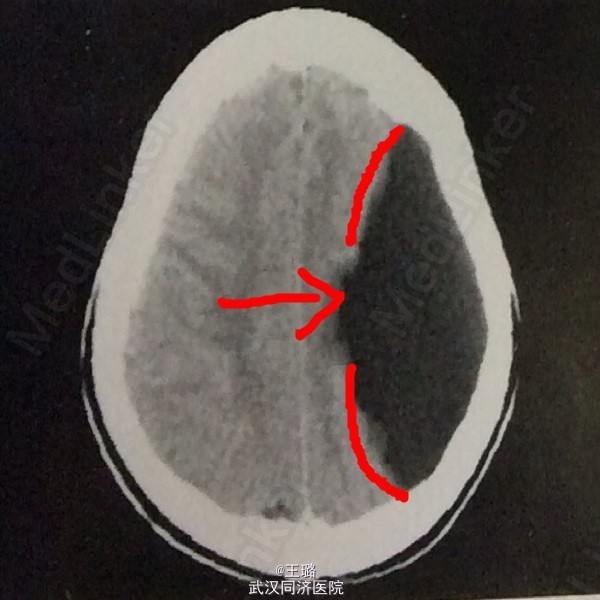

脑裂畸形

患者,男,13岁,自幼上下肢活动受限,近期由于头痛、头晕入院。入院体检示全身运动不协调,肌张力异常,部分感觉缺如。实验室检查:中性粒细胞增高,红细胞降低,血生化正常,肝肾功能正常。CT示:左侧大脑半球横贯宽裂隙,透明隔缺如,外侧有低密度囊状影。诊断为:脑裂畸形。该病为最严重的神经元移行异常,常伴有透明隔缺如,可出现智力低下、癫痫发作以及肢体瘫痪。